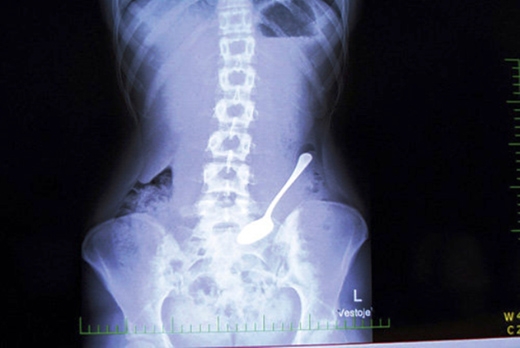

1. Cái muỗng gần xương chậu